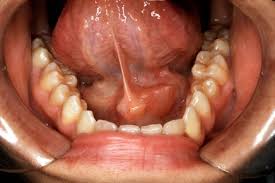

- Mucocele (Mucus-Retention Cyst): A cystic lesion filled with mucous material, often resulting from trauma or obstruction of the salivary gland duct.